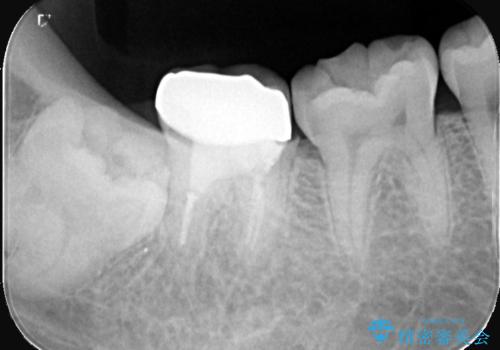

- 「銀歯を白くしたい」を主訴に来院された患者様です。

銀歯と虫歯を除去後、オールセラミッククラウンで治療を行いました。

銀歯を除去後、オールセラミッククラウンで治療を行いました。

根管治療はご希望されなかったため被せ物のみ治療しています。

クリアランスが少なかったため支台歯の真ん中に保持溝を入れています。